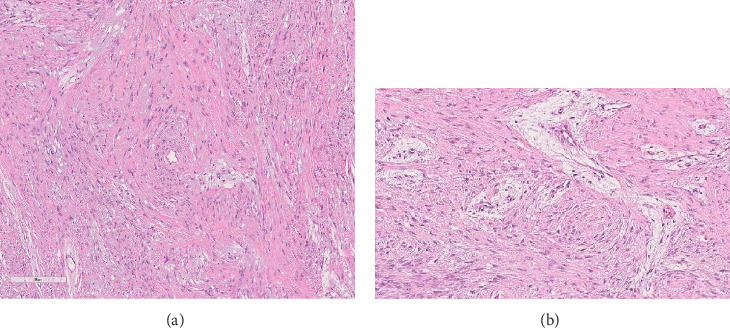

大多数原发性甲状旁腺功能亢进(PHPT)是散发性的,由甲状旁腺瘤引起。遗传性形式可能发生在高达10%的PHPT患者中,更常见于年轻患者。甲状旁腺功能亢进-下颌肿瘤(HPT-JT)综合征的特征是高达95%的患者有PHPT, 25%-50%的患者有颌骨骨化纤维瘤。我们描述的情况下,35岁的男性从孟加拉国转介到我们医院,由于一个巨大的右下颌骨肿胀:一个罕见的非骨化纤维瘤下颌骨被诊断。由于功能性阳痿,左肩磁共振成像(MRI)显示肱骨近端多分叶囊肿样病变,诊断为棕色肿瘤(BT)。随后的测试突出高钙血症和低磷血症与高甲状旁腺激素水平。鉴定出CDC73的杂合致病变异c96 >a p.Trp32Ter。据我们所知,这是第一例与CDC73致病变异相关的HPT-JT综合征,与手臂的BT和罕见的下颌骨非骨化纤维瘤相关。

Most cases of primary hyperparathyroidism (PHPT) are sporadic and are caused by parathyroid adenomas. Hereditary forms may occur in up to 10% of PHPT patients and are more frequent in younger patients. The hyperparathyroidism-jaw tumor (HPT-JT) syndrome is characterized by PHPT in up to 95% of patients and ossifying fibromas in the jaw in 25%-50%. We describe the case of a 35-year-old male from Bangladesh referred to our hospital due to a voluminous right mandibular swelling: a rare nonossifying fibroma of the mandible was diagnosed. Due to functional impotence, a left shoulder magnetic resonance imaging (MRI) was performed with evidence of a pluri-lobulated cyst-like lesion in the proximal humeral area diagnosed as a brown tumor (BT). Subsequent tests highlighted hypercalcemia and hypophosphatemia with high PTH levels. A heterozygous CDC73 pathogenic variant c.96>A p.Trp32Ter was identified. To the best of our knowledge, this is the first reported case of HPT-JT syndrome related to a CDC73 pathogenic variant, associated to a BT of the arm and a rare nonossifying fibroma of the mandible.